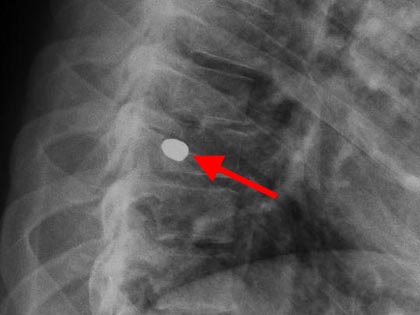

Schmerzsyndrome der Wirbelsäule; Bandscheibenvorfall; Verschleiß der Bandscheiben; Spinalkanalstenose (Verengung des Wirbelkanals); Instabilitäten; Spondylolisthesis (Wirbelgleiten), Myelopathie (Schädigung des Rückenmarkes); Querschnittslähmung; Erkrankungen bei Kinder und Heranwachsenden (z. B. Formveränderungen, Skoliosen, Kyphosen, angeborene Wachstumsstörungen, Verletzungen, Entzündungen, Tumore und Metastasen); Verletzungen des Rückenmarks; Wirbelkörperbrüche; Deformitäten (Formveränderungen, Skoliose, Kyphose); Tumore und Metastasen; Infektionen; Spondylodiszitis (Infektion von Bandscheiben und Wirbelkörper); rheumatische Instabilitäten der Halswirbelsäule sowie zwischen Kopf und Halswirbelsäule; rheumatische Veränderungen der Brust- und Lendenwirbelsäule (z. B. Morbus Bechterew);Verengungen des Foramen magnum; muskulärer Schiefhals; Syndrome durch die erste Rippe; Deformitäten des Thorax (z. B. Trichterbrust, Kielbrust); Erkrankungen und Verletzungen der Rippen; etc.